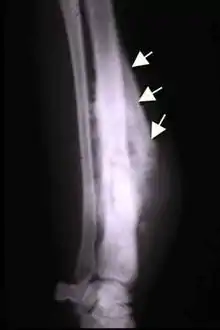

Codman triangle

Codman triangle (previously referred to as Codman's triangle) is the triangular area of new subperiosteal bone that is created when a lesion, often a tumour, raises the periosteum away from the bone.[1] A Codman triangle is not actually a full triangle. Instead, it is often a pseudotriangle on radiographic findings, with ossification on the original bone and one additional side of the triangle, which forms a two sided triangle with one open side. This two sided appearance is generated due to a tumor (or growth) that is growing at a rate which is faster than the periosteum can grow or expand, so instead of dimpling, the periosteum tears away and provides ossification on the second edge of the triangle.[2] The advancing tumour displaces the perisosteum away from the bone medulla. The displaced and now lateral periosteum attempts to regenerate underlying bone. This describes a periosteal reaction.

The main causes for this sign are osteosarcoma, Ewing's sarcoma, eumycetoma, and a subperiosteal abscess.[3][4]